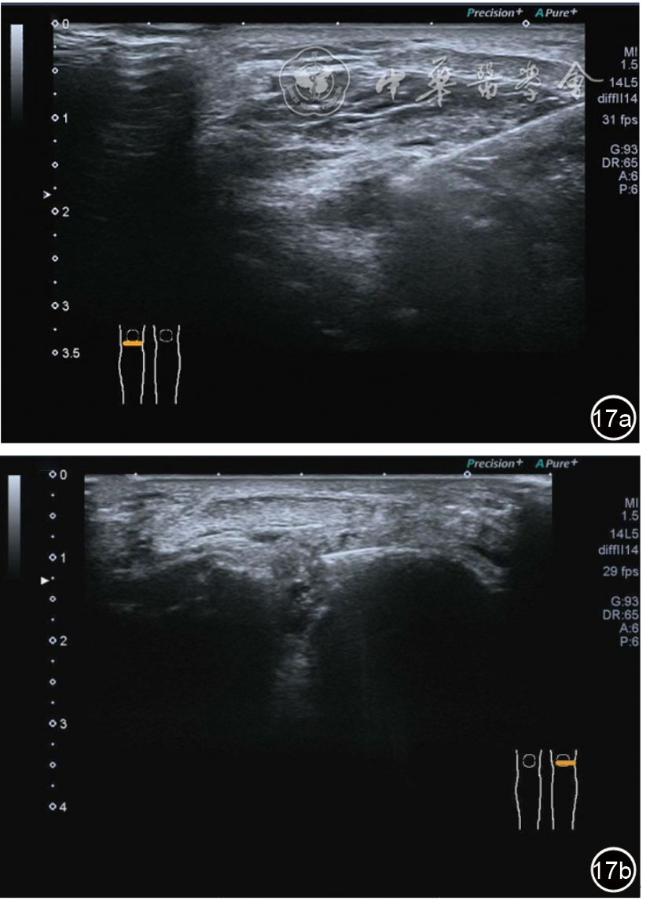

(五)超声影像学表现

患者采取侧卧位,患肢在上,屈膝20°。应用10~18 MHz高频线阵探头,扫查深度1~3 mm。长轴和短轴结合双侧对比扫查。超声影像学所见:短轴可见卡压腓总神经近端增粗,面积增大;长轴可见腓总神经卡压处变细,其近侧肿胀、回声减低,而在卡压远侧则表现正常(图35);一些受压严重者可以出现神经周围积液,卡压神经部位的筋膜增厚(图36);受压神经内血流增加对临床诊断意义更大(图37);探头在病变神经处加压常可引起神经刺激症状。腓总神经支配的肌肉有失神经支配改变,表现为肌肉回声增高和肌肉萎缩(图38)。

图35 超声短轴可见卡压腓总神经近端增粗,面积增大;长轴可见腓总神经卡压处变细,其近侧肿胀、回声减低

图36 超声图像示腓总神经周围积液,卡压神经部位的筋膜增厚